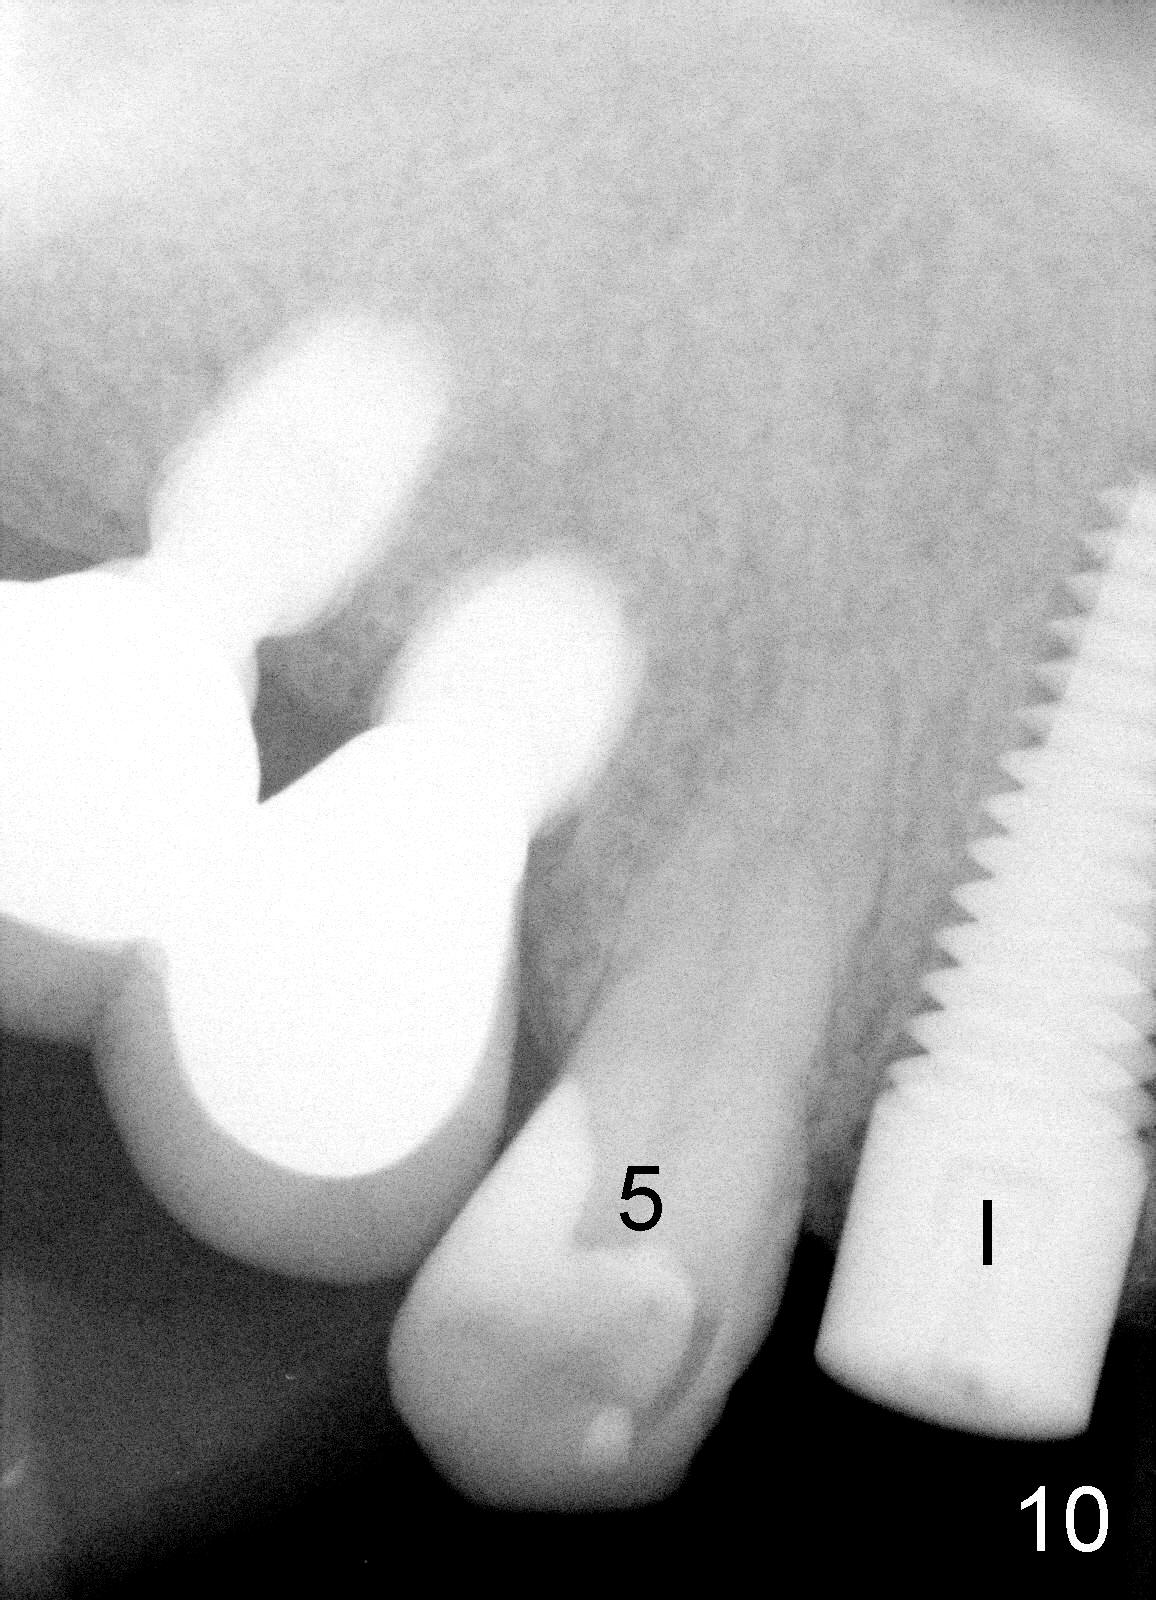

One week after #6 immediate implant placement, the patient is doing well. There is apparently enough clearance between the tooth #5 and the implant in term of bone (Fig.10, compare to Fig.4) and soft tissue (Fig.11, compare to Fig.3).